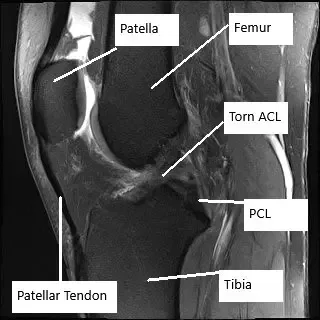

Resonancia magnética de la rodilla en la sección sagital muestra rotura del LCA.

La resonancia magnética de la rodilla derecha reveló un desgarro del LCA de grosor total con un patrón de contusión ósea indicativo de una reciente traslación tibial anterior. La rotura del LCA ha avanzado ahora a un grosor total y es peor en comparación con el estudio anterior. Desgarro del menisco medial y lateral, progresivo en gravedad desde el estudio anterior.